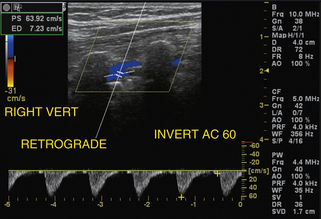

Более распространенной находкой, чем отсутствие кровотока в позвоночной артерии, является обратный кровоток или подключичное обкрадывание. Это простой диагноз, который можно поставить с помощью дуплексного ультразвукового исследования, поскольку ретроградный кровоток в позвоночной артерии наблюдается на протяжении всего сердечного цикла ( рис. 11-10 ), хотя следует соблюдать осторожность, чтобы не спутать сигнал пульсирующего потока в позвоночной вене с обратным потоком в позвоночной артерии. В 90% случаев обратный позвоночный поток (за счет подключичного обкрадывания) возникает с левой стороны. У пациентов с подключичной обкрадой также должна быть возможность документировать аномальные формы скорости кровотока в дистальном сегменте пораженной подключичной артерии ( рис. 11-11 ). При обнаружении реверса позвоночного кровотока с правой стороны важно определить, является ли источником обкрадывания подключичная артерия, которая влияет только на кровоток в позвоночной артерии, или безымянная артерия, оказывающая существенное влияние как на правую общую сонную артерию, так и на безымянную артерию, которая оказывает существенное влияние как на правую общую сонную артерию, так и на и позвоночные артерии. Обычно у пациентов с подключичным обкрадыванием разница систолического давления между нормальной и пораженной руками превышает 15–20 мм рт. ст. Дополнительным признаком может быть увеличение размера позвоночной артерии и сильный компенсаторный кровоток, контрлатеральный подключичному обкраду; Однако из-за большой вариабельности нормального размера позвоночной артерии и скорости кровотока, упомянутой ранее, этот результат не является диагностическим как изолированное наблюдение.

РИСУНОК 11-11. Результаты допплерографии при подключичном обкрадении. Спектральный допплеровский сигнал скорости от дистальной подключичной артерии у пациента с подключичной обкрадой показан на рисунке 11-10 . Форма волны монофазная с задержкой систолического подъема вверх и затухающая, что характерно для тяжелой проксимальной обструкции в месте отхождения подключичной артерии.